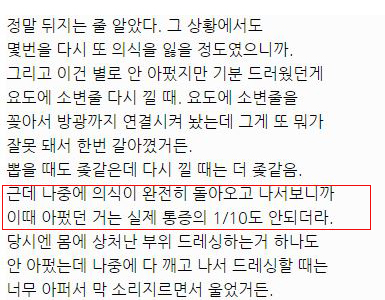

대단한 얘기는 아니지만 중환자실에 3주동안 무의식으로 있었던 썰 풀어볼게